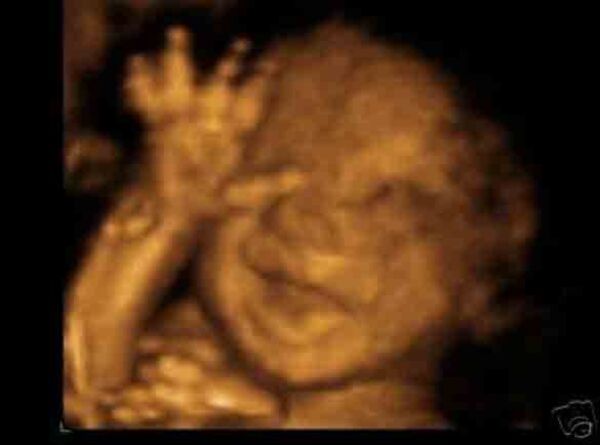

Bebekler anne karnında ne yapar?